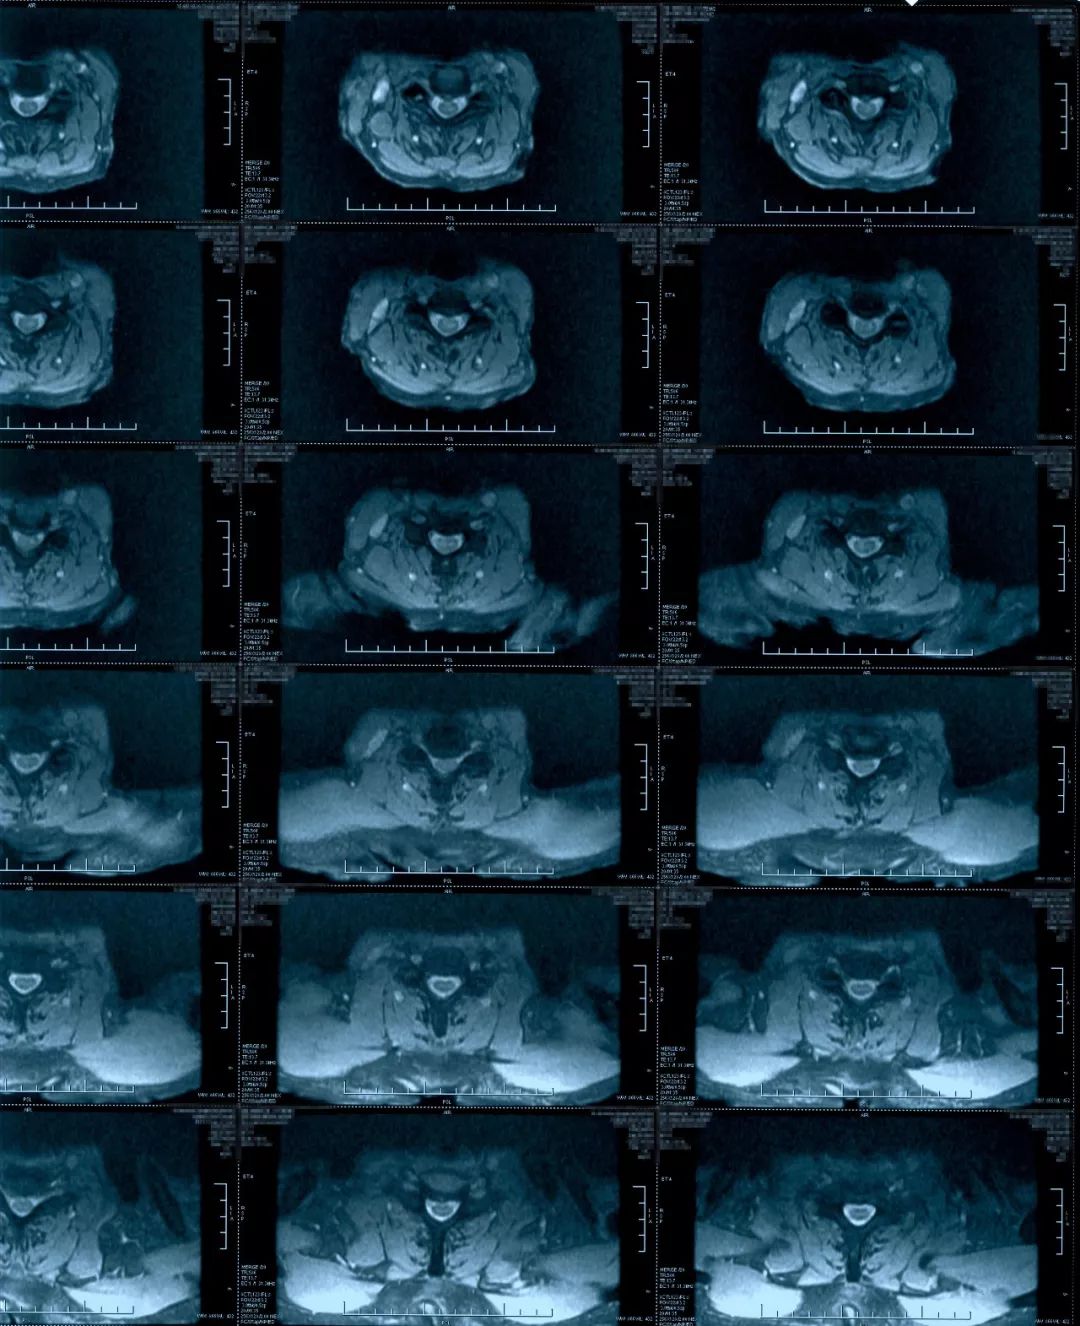

这个病人转到我们科的时候,影像上表现椎管狭窄,脊髓有长阶段的脊髓水肿信号,有黄韧带增厚,后方的间盘有轻度突出,骨质增生等等。

治疗前影像学资料